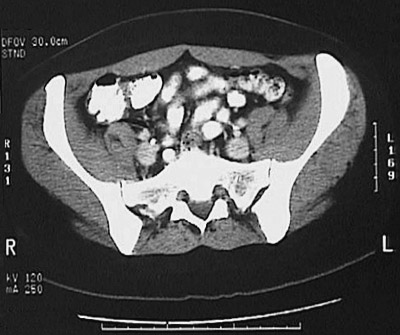

[L5] This is a normal abdominal CT scan with contrast demonstrating the lower abdomen with the small intestine and rectus abdominis muscle and iliacus muscle and gluteus medius muscle and multifidus muscle and ilium and sacroiliac joint and psoas muscle .